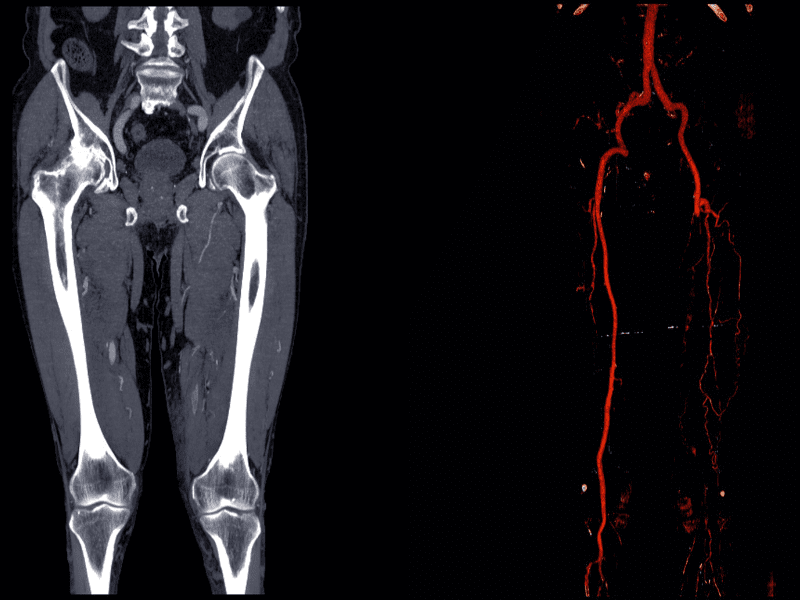

Il Metodo ASVAL Napoli (Associazione per la Scleroterapia Video-Assisted) sviluppato dal Dr. Demetrio Guarnaccia è una tecnica innovativa ed avanzata utilizzata per trattare le patologie venose, in particolare quelle legate all’insufficienza venosa e alle varici.

Il metodo ASVAL Napoli unisce la scleroterapia (l’iniezione di sostanze per sigillare le vene danneggiate) con l’ausilio della video-assistenza, migliorando la precisione del trattamento.